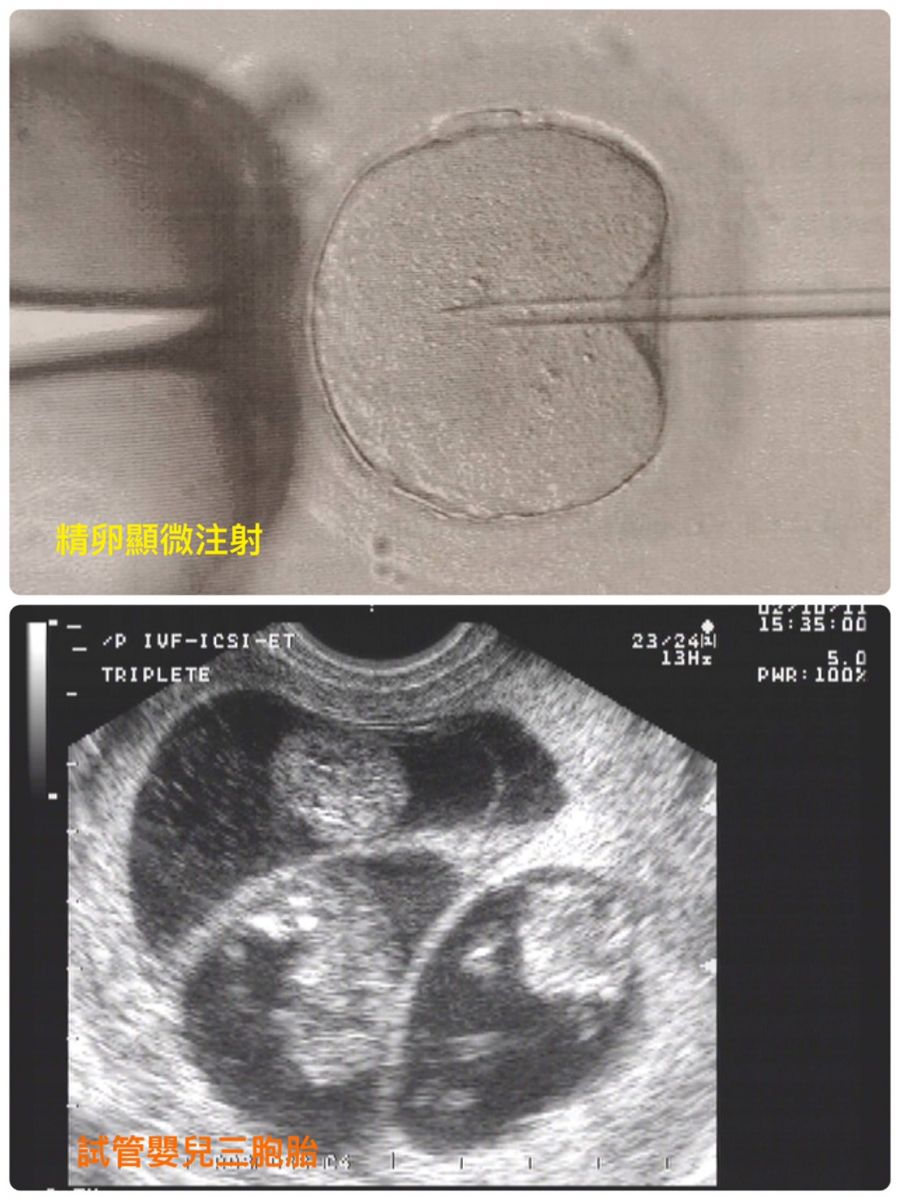

因為社會環境法律規範以及經濟模式的發展,造成一般人都晚婚,根據內政部統計初次懷孕的女性年齡為31.0歲。隨之而來的是懷孕率的下降甚至造成不孕,而這些問題已經影響了家庭的結構穩定,不但造成容易造成教育方向過度集中, 進而影響社會結構穩定與經濟發展的限制 ,最後影響到國力興衰。台灣的生育率是全世界倒數第一名,早已不是新聞。 經過非常多人的努力,政府終於從善如流,修正了之前鳥籠的補助方案。把原來只有中低收入戶才能夠申請,改為大家通通有獎,只要未滿45足歲已婚女性,中低收入戶一次最多15萬元。如果不是中低收入戶的人也會補助約6成,一次最多10萬元。而且開放名額由原來的一年全台灣限20個改為一年23000到28000個。實施的時間從今年的7月1號開始,在全國93所人工生殖機構實施。除了為以前因為經濟問題沒有辦法做試管,仍然不孕症的女生覺得生不逢時感到惋惜之外,也非常替準備要做人工生殖的不孕症女生感到高興,拍手叫好。